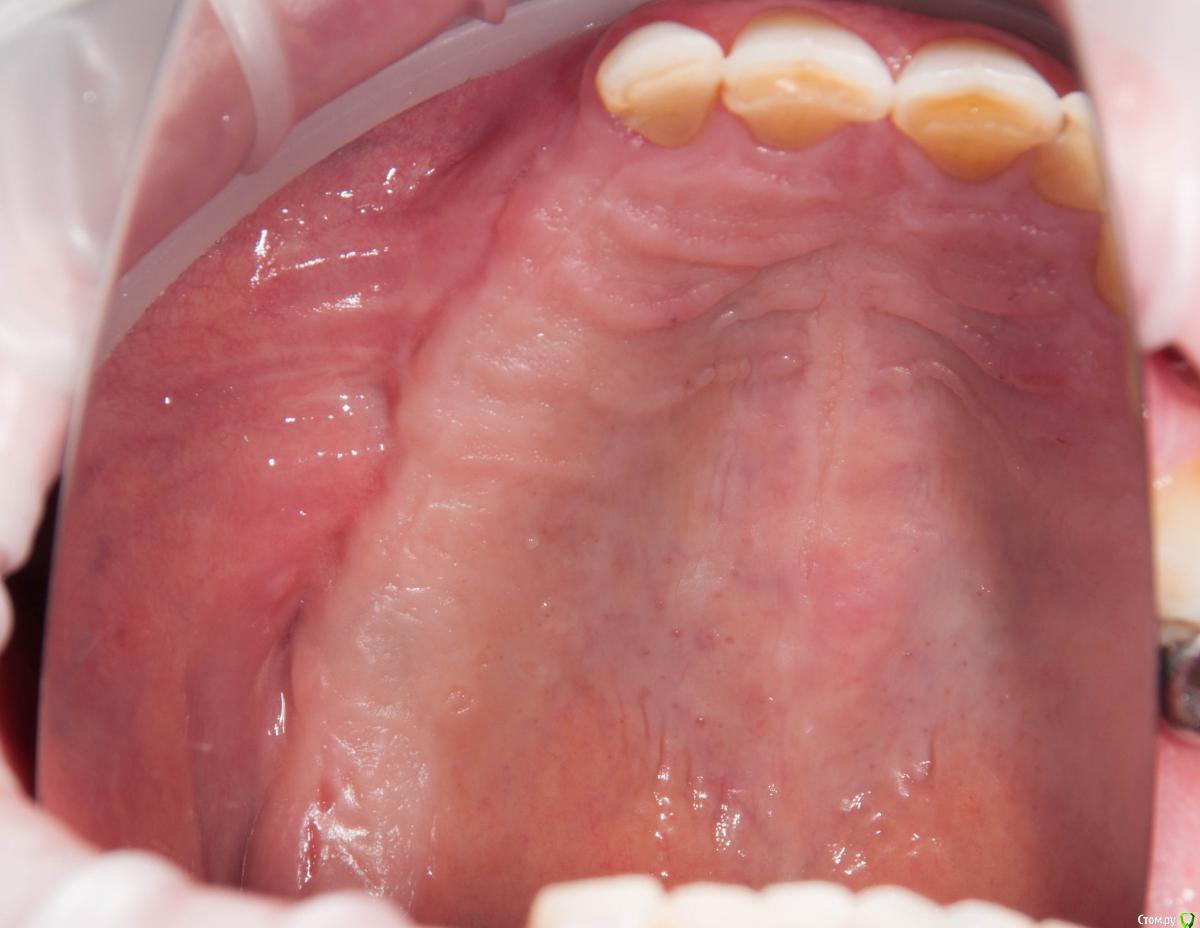

kamranchick Опубликовано 4 мая, 2018 Поделиться Опубликовано 4 мая, 2018 Обратился пациент после очередной халтуры которыми радуют меня коллеги из соседних клиник)фотопротокол ни как у Сашки Гудкова но более-менее понятно))Обратился пациент, в соседней клинике удаляли зуб, корень протолкнули в пазуху, далее пациент попал в ЧЛХ, там сделали радикальную гайморотомию, все достали, и вот попал пациент ко мне, так как в другой клинике сказали что у вас тут залу*а, а не кость, ну и погнали.1. пытался остро отслоиться, перфа на перфе, закрывал prf, мембранами, губками, стики бон + синус имплантация. ожидание 9 месяцев2. Пластика мягких тканей ожидание 2 месяца. 13 Ссылка на комментарий

kamranchick Опубликовано 5 мая, 2018 Автор Поделиться Опубликовано 5 мая, 2018 Гребень, конечно, был ужасный. Симпатично. Почему Паллачи?Я бы не сказал что это прям Палаччи)бугра нету так такого... плюс тут апикально надо было смещать, было 2 вариант, стрип, либо сдт около формиков, решил остановиться на таком варианте. Ссылка на комментарий

Kazankov.Egor Опубликовано 5 мая, 2018 Поделиться Опубликовано 5 мая, 2018 Обратился пациент после очередной халтуры которыми радуют меня коллеги из соседних клиник)фотопротокол ни как у Сашки Гудкова но более-менее понятно))Обратился пациент, в соседней клинике удаляли зуб, корень протолкнули в пазуху, далее пациент попал в ЧЛХ, там сделали радикальную гайморотомию, все достали, и вот попал пациент ко мне, так как в другой клинике сказали что у вас тут залу*а, а не кость, ну и погнали.1. пытался остро отслоиться, перфа на перфе, закрывал prf, мембранами, губками, стики бон + синус имплантация. ожидание 9 месяцев2. Пластика мягких тканей ожидание 2 месяца.К кому сходить на мягкие ткани? Посоветуйте пожалуйста. Ссылка на комментарий